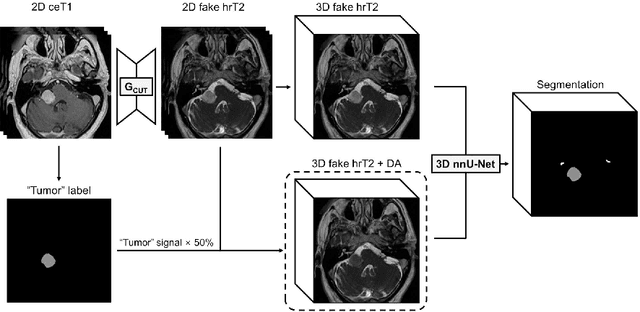

Abstract:Domain Adaptation (DA) has recently raised strong interests in the medical imaging community. While a large variety of DA techniques has been proposed for image segmentation, most of these techniques have been validated either on private datasets or on small publicly available datasets. Moreover, these datasets mostly addressed single-class problems. To tackle these limitations, the Cross-Modality Domain Adaptation (crossMoDA) challenge was organised in conjunction with the 24th International Conference on Medical Image Computing and Computer Assisted Intervention (MICCAI 2021). CrossMoDA is the first large and multi-class benchmark for unsupervised cross-modality DA. The challenge's goal is to segment two key brain structures involved in the follow-up and treatment planning of vestibular schwannoma (VS): the VS and the cochleas. Currently, the diagnosis and surveillance in patients with VS are performed using contrast-enhanced T1 (ceT1) MRI. However, there is growing interest in using non-contrast sequences such as high-resolution T2 (hrT2) MRI. Therefore, we created an unsupervised cross-modality segmentation benchmark. The training set provides annotated ceT1 (N=105) and unpaired non-annotated hrT2 (N=105). The aim was to automatically perform unilateral VS and bilateral cochlea segmentation on hrT2 as provided in the testing set (N=137). A total of 16 teams submitted their algorithm for the evaluation phase. The level of performance reached by the top-performing teams is strikingly high (best median Dice - VS:88.4%; Cochleas:85.7%) and close to full supervision (median Dice - VS:92.5%; Cochleas:87.7%). All top-performing methods made use of an image-to-image translation approach to transform the source-domain images into pseudo-target-domain images. A segmentation network was then trained using these generated images and the manual annotations provided for the source image.

Abstract:The purpose of this study is to apply and evaluate out-of-the-box deep learning frameworks for the crossMoDA challenge. We use the CUT model for domain adaptation from contrast-enhanced T1 MR to high-resolution T2 MR. As data augmentation, we generated additional images with vestibular schwannomas with lower signal intensity. For the segmentation task, we use the nnU-Net framework. Our final submission achieved a mean Dice score of 0.8299 (0.0465) in the validation phase.